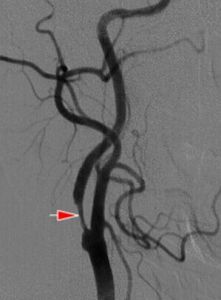

ICA狹窄率的常用測量方法有3中,即NASCET法,ECST法和CC法。NASCET法套用最廣泛,除ICA外,尚可套用於椎-基底動脈和顱內ICA-MCA系統,其公式是:狹窄率=(狹窄遠端正常直徑-狹窄段最窄直徑)/狹窄遠端正常直徑×100%。

ECST法的公式是:狹窄率=(狹窄段估計的正常直徑-狹窄段最窄直徑)/狹窄段估計的正常直徑×100%。

CC法的公式是:狹窄率=(頸總動脈直徑-狹窄段直徑)/頸總動脈直徑×100%。

腦血管狹窄診斷方法

依據臨床表現及輔助檢查確診。無創檢查:超音波及核磁共振血管造影(MRA)。有創檢查:腦血管造影。腦供血動脈超聲檢查